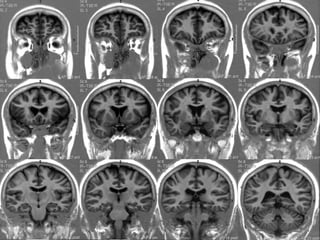

Anatomia cerebral

Gânglios da Base

• Tecido de substância cinzenta sub cortical

simétrico, localizados nas superfícies inferiores

dos hemisférios cerebrais.

• Núcleos lenticulares ( putamen e globus pálido),

núcleo caudado, claustro e amígdala.

Núcleos lenticulares.

• Biconvexo , envolto por substância branca,

• Cápsula externa ( separa do Claustro ),

• Cápsula Extrema ( separa claustro da ínsula ),

• Cápsula interna ( braço anterior , joelho e

braço posterior ).

• Putamen ( lateral , maior e mais escuro ) / globo pálido.

Diencéfalo

• Epitálamo ( núcleos e comissura habenulares ,

pineal e comissura posterior ).

• Tálamo ( 80 % do diencéfalo ),

•   Hipotálamo ,

•   Subtálamo

Tálamo

• Massas nucleares , grandes e dispostas

de forma simétrica.

• Substância cinzenta , mede 3,0 x 1,5 cm ,

• Aglomerações de neurônios e núcleos,

• Forma a parede lateral do III ventrículo.